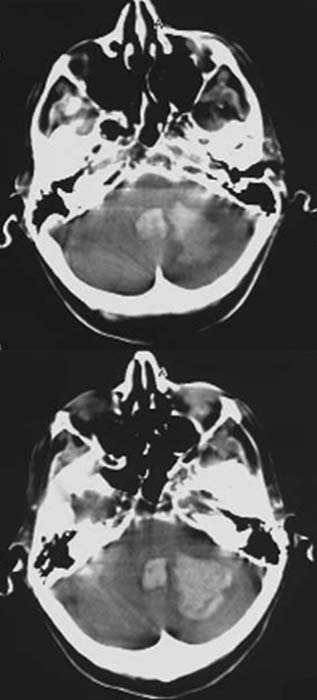

CCT nativ (ohne Kontrastmittel).

Hyperdense

(60-80HE) Raumforderung in der linken Kleinhirnhemisphäre mit perifokaler

Hyperdensivität.

Hypodenser

Verhalt im 4. Ventrikel.

Verstrichene

Gyri und Sulci der linken Kleinhirnhemisphäre.

Hypertensive

Hirnmassenblutung der Kleinhirnhemisphere links mit perifokalem

Ödem.

Einblutung in

den 4. Ventrikel

Hirnödem v.a. der linken Kleinhirntonsille